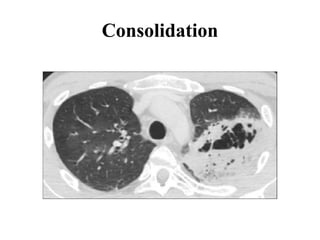

INCREASED ATTENUATION

PATTERN

Increase in density of the lung parenchyma

• Increased Lung Attenuation Is Called As Ground

Glass Opacity - If There Is A Hazy Increase In Lung

Opacity Without Obscuration Of Underlying Vessels

And

• Consolidation If The Increase In Lung Opacity

Obscures The Vessels

• In Both Ground Glass And Consolidation The

Increase In Lung Density Is The Replacement Of Air

In The Alveoli By Fluid, cells or Fibrosis.

• Ground Glass Opacity:-density Of Intrabronchial Air

Appears Darker As The Air In The Surrounding

Alveoli(called As Dark Bronchus Sign)

• Consolidation:-exclusively Air Left In Intrabronchial

Called As Air Bronchus Sign

Fibrosis

Consolidation